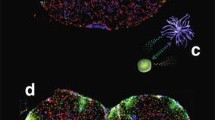

Prior to transplantation, the BM-M were exposed astrocyte conditioned medium and cell viability measurement was performed (BM-M viability> 90%). These conditioned BM-M were positive for CD11b, CD45, CD68 and F4/80, which are general microglia markers (Fig. 1). In addition, we stained the cells for M1 and M2 markers and found the BM-M to be mainly of a microglia-M2 phenotype (CD16, CD64, CD169, CD124, CD204, CD206 and dectin). M1 markers (CD 80, CD86, and MHCII) expression levels were low (< 30%).

Characterization of BM-M phenotype by flow cytometry. BM-M were positive for CD11b, CD45, CD68, CD206 and F4/80, which are general microglia markers. Levels of M2 specific microglia markers (CD16, CD64, CD169, CD124, CD204 and dectin) were higher than M1 markers (CD80, CD86, and MHCII) indicating the prevalence of a microglia-M2 phenotype. At the top right a representative image of the transplanted BM-M is shown